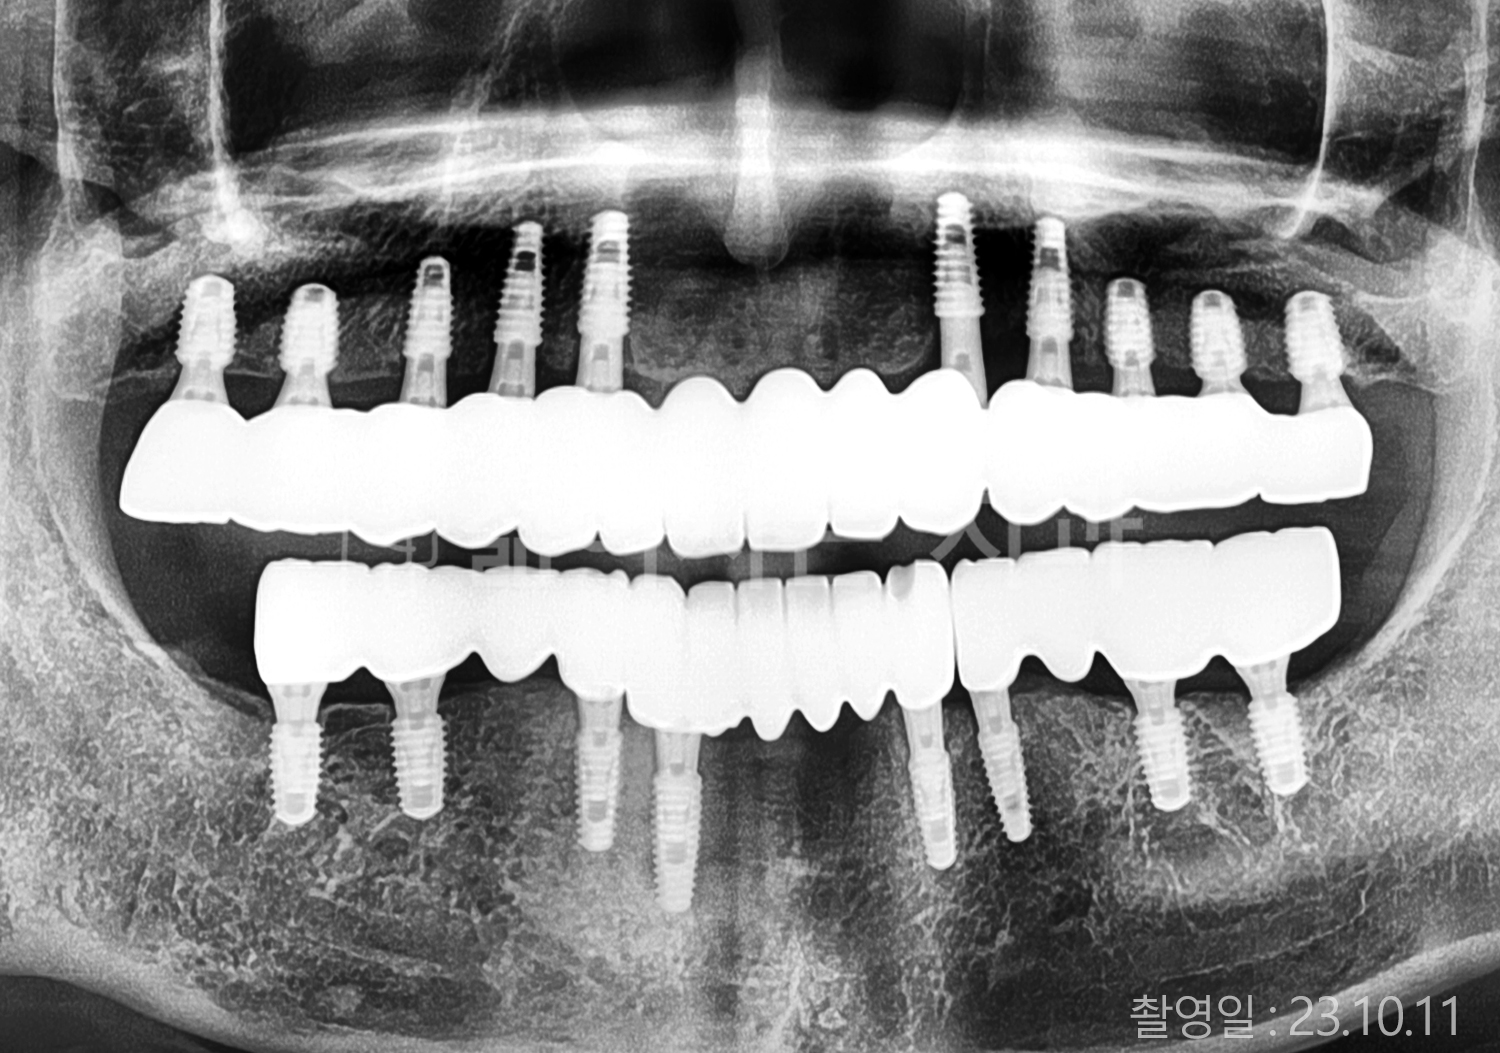

• 40대 전체치아 10개 이상 임플란트

• 70대 당뇨 전체치아 10개 이상 임플란트

• 60대 전체치아 10개 이상 임플란트

• 60대 고혈압, 당뇨, 고지혈증 전체치아 10개 이상 임플란트

• 50대 전체치아 10개 이상 임플란트

• 70대 고혈압, 당뇨 전체치아 10개 이상 임플란트

• 60대 고혈압 전체치아 10개 이상 임플란트

• 50대 고혈압, 당뇨, 고지혈증 전체치아 10개 이상 임플란트

• 60대 고혈압, 고지혈증 전체치아 10개 이상 임플란트